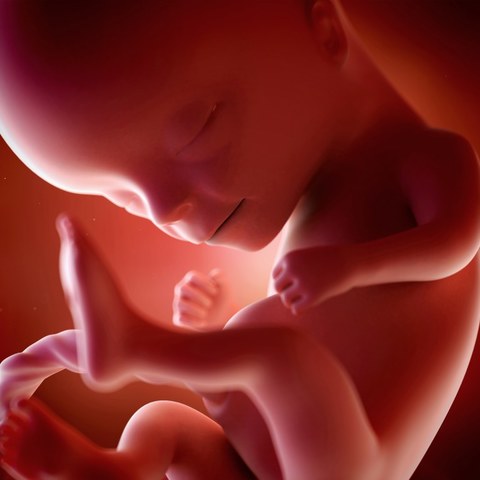

• 5 MESES

5 MESES

Feto mide 20 cm aprox

La coclea que es el órgano d el audición, ha alcanzado su tamaño adulto dentro del oído, ahora el feto responderá a una gama de sonidos cada vez mayor.

Comienza a crecer pelo sobre el cuero cabelludo

Todas las capas y estructuras de la piel están presentes inclusive folículos pilosos y glándulas.

Los pulmones adquieren cierta capacidad para respirar aire, se considera una edad viable para vivir fuera del útero.